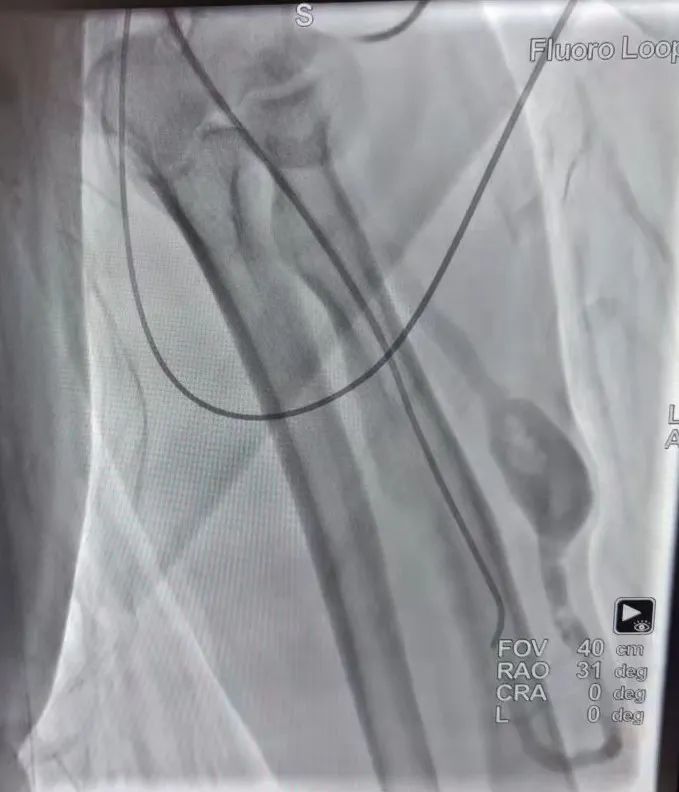

手術(shù)前造影 手術(shù)后造影